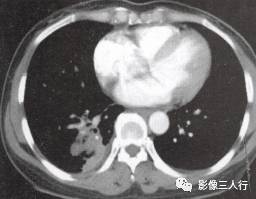

原发性肺淋巴瘤在影像上可呈现肺实质内或肺门旁单发的圆形、卵圆形、分叶状、密度 均匀、边缘清晰的肿块影,其内可见空气支气管征,可累及一叶或一侧肺。继发性肺淋巴瘤 肺内病变包括下面几种。①混合型:肺内病变表现形式多样,可出现多发的肿块结节、斑片 状渗出或实变影以及增粗的支气管血管束,呈两种或两种以上的混合形式存在,可见空气支气管征。见图13。②肿块(结节)型:双侧肺内散在分布的多发性肿块结节,直径在1〜 5cm,多数为类圆形,可见空气支气管征。见图14。③肺炎肺泡型:单侧或双侧肺野分 布的斑片状渗出或实变影,中心密度高,周边密度低,可见空气支气管征。见图15。 ④支气管血管淋巴管型:肺内弥漫性或节段性支气管血管束增粗。⑤粟粒型:表现为双肺弥 漫分布的针尖样大小的阴影,边界清楚,无融合。